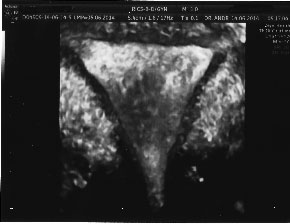

![]() | ![]() |

| Cavitate uterina de aspect normal. Arhiva personala Dr. Lara Andronescu | Cavitate uterina de aspect normal. Arhiva personala Dr. Lara Andronescu |